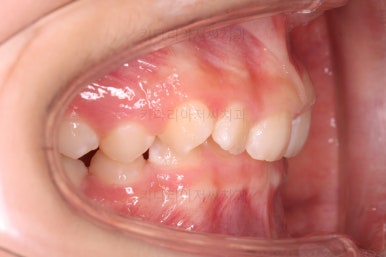

마무리를 해줍니다.

앞니 각도가 매우 좋아졌고요.(옥니 개선) 위 아래 앞니가 덮는 정도도 개선되었어요.(과개교합, 딥바이트)

엉성했던 어금니 맞물림도 매우 좋아졌어요.(앵글씨 2급 부정교합)

특히 옆라인에서 아래턱이 살아나면서 입매가 매우 예뻐졌어요.

부산교정병원 전후사진을 비교해 볼게요.

협조도가 요구되는 장치를 잘 못끼는 바람에 중간에 우여곡절이 있었고 힘든 과정도 있었지만 비교적 만족스러운 치료를 할 수 있었어요.